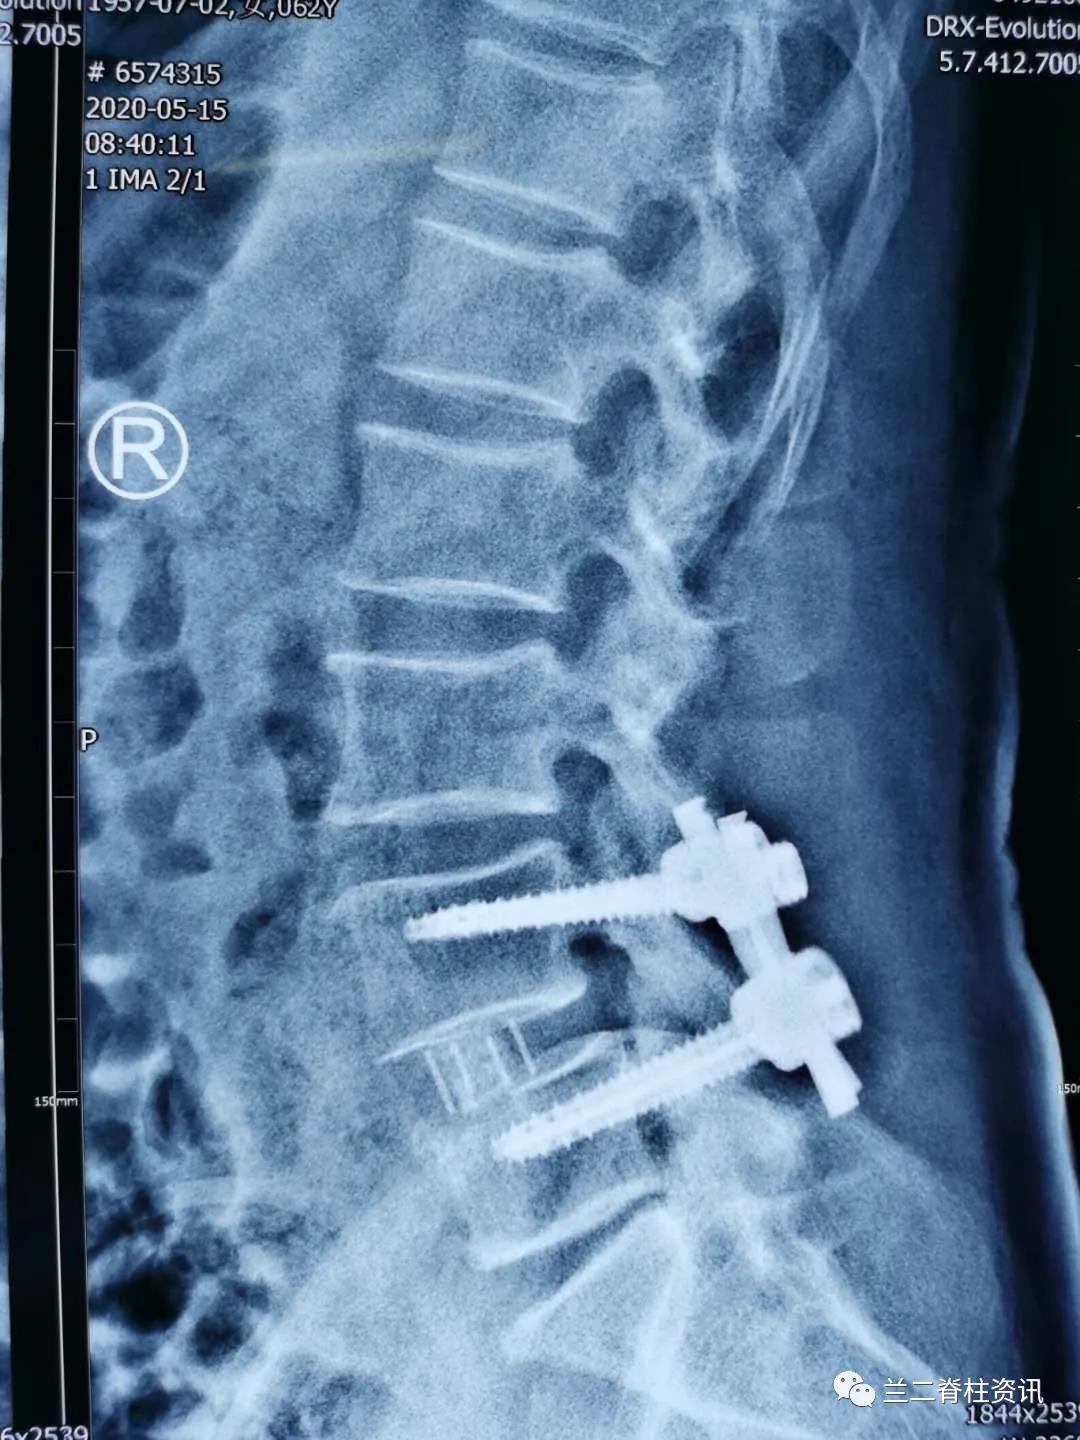

通常OLIF手术需用侧卧位微创植入融合器后变换体位(俯卧位)植入经皮椎弓根钉,该患者采用单一体位OLIF 融合术 ,利用c臂“徒手”植入经皮椎弓根螺钉。该技术允许在单一体位下“毕其功于一役”,简化了手术流程,缩短了手术时间,减少感染风险,降低变换体位导致的麻醉脱管等并发症,促进了术后康复,大大缩短了手术时间,真正实现了“高效、可视、精准、安全”的脊柱微创治疗理念。本例手术的成果,也标志着我院骨科在脊柱微创领域方面走在了国内前沿。